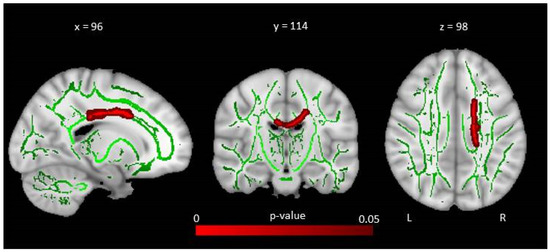

6.2. White Matter